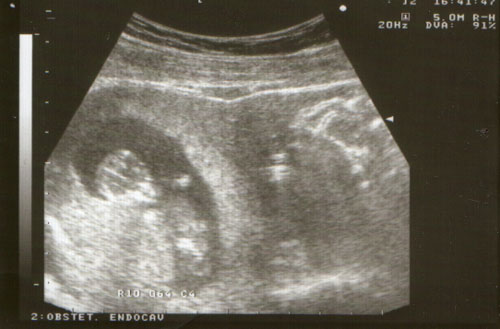

Ja a védőnő szeptember 28. írt a kiskönyvbe. +7 nap mínusz 3 hónap a szokásos módon számolta. Viszont a babanet kalkulátorra szept. 27. dobott ki.

Mind1 lehet, hogy 1 héttel hamarabb születik, mint Manó.